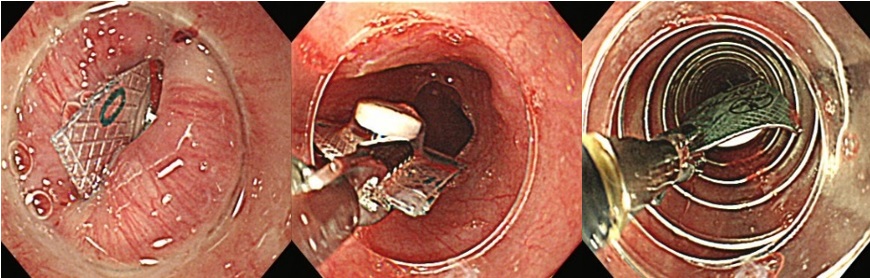

『薬パッケージの誤飲に対する異物除去術』

大腸ポリープ切除術、早期癌に対する内視鏡的粘膜剥離術、胃潰瘍などからの出血に対する内視鏡的止血術、食道静脈瘤からの出血に対する結紮術、アニサキス(寄生虫)や薬パッケージの誤飲に対する異物摘出術など。また胆道・膵臓系では、内視鏡を用いた胆石除去や、胆道感染や癌に伴う黄疸に対する内視鏡的な減黄術(ステント留置術)など各種行っております。